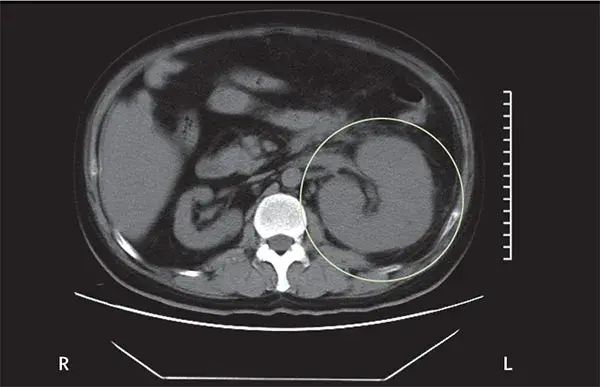

Main Trial: Micofenolato para Nefropatia por IgA

Main Trial: Micofenolato para Nefropatia por IgA

O tratamento da Nefropatia por IgA está longe de ser simples, confere o Trial mais recente que avaliou eficácia do Micofenolato.